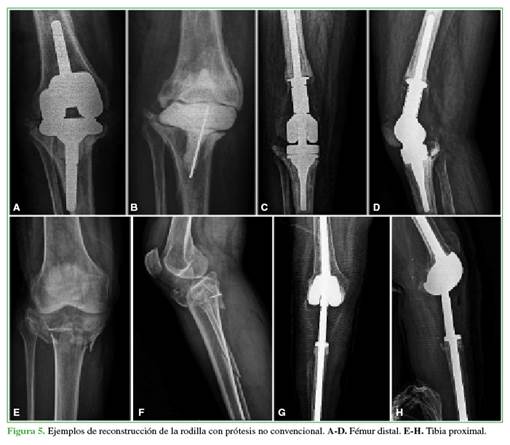

Los tipos de prótesis utilizados para la reconstrucción tenían alguna variación y fueron: siete prótesis IOT-HCFMUSP Modular System (MDT Implantes, Rio Claro, SP, Brasil), tres Megasystem-C (Waldemar Link GmbH & Co, Hamburgo, Alemania) y dos OSSTM Orthopedic Salvage System (Biomet, Warsaw, IN, EE.UU.).

En detalle, se implantaron nueve endoprótesis de fémur distal (75%), dos de tibia proximal (16,7%) y una de fémur distal y tibia proximal (8,3%). Cuando se colocaba una prótesis de tibia proximal, la reconstrucción del mecanismo extensor se realizaba suturando el tendón rotuliano en el componente tibial, que proporciona orificios de fijación en su parte proximal, y se creaba un colgajo rotatorio de gemelo interno para reforzar la reinserción del tendón. No se efectuaron osteotomías de rótula. Siempre se utilizaron tallos cementados tanto en el fémur como en la tibia. Se colocaron prótesis abisagradas (MDT) en siete casos y una bisagra rotatoria (Waldemar Link GmbH & Co y Biomet) en cinco.